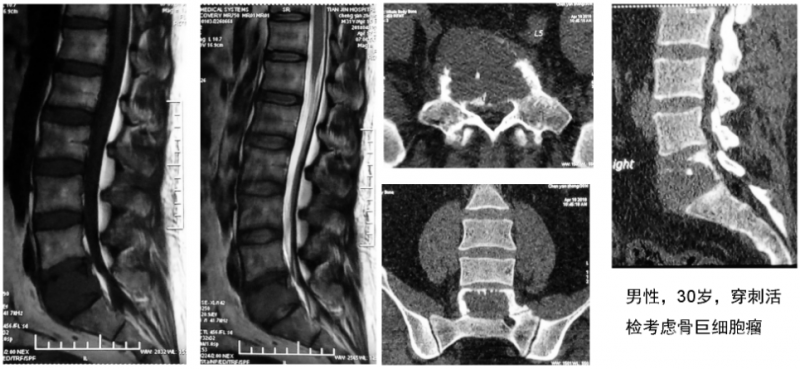

此前,有一例腰5椎体肿瘤患者在前路切除后进行椎体重建,以往临床上都是在术中给患者翻身进行后路固定。马信龙教授团队在做术前设计时,就给这名患者设计了个性化人工椎体,预留了假体与骨结合部位从前向后打椎弓根钉的孔,不需要患者翻身进行后路固定就获得了稳定性,临床效果令人满意。此例前路腰骶部病变切除后采用自主设计的3D打印假体重建椎体稳定性的病例,尚属国际首例。

一例前路腰骶部病变患者术前影像片

为此例前路腰骶部病变患者设计的个性化腰骶部假体

此例前路腰骶部病变患者切除重建术后影像片